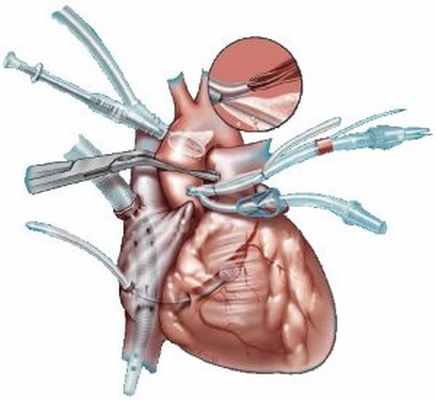

Хирургическое вмешательство является «золотым стандартом» лечения обструктивной ГКМП. В 1961 г. A. Morrow и E. Brockenbrough [13] описали алгоритм выполнения септальной миоэктомии (МЭ), однако выполнена данная операция была впервые еще в 1958 г. английским кардиохирургом W. Cleland [14].

Стандартом хирургического лечения пациентов с обструктивной формой ГКМП, у которых аорто-желудочковый градиент давления составляет 50 мм рт.ст. и более (в покое или при физической нагрузке), вот уже почти 50 лет является септальная миоэктомия (МЭ) [35, 52, 56]. В течение последних лет послеоперационная выживаемость после септальной МЭ составляет 99, 98 и 95% в течение 1, 5 и 10 лет соответственно [57]. Такого результата удалось добиться благодаря совершенствованию хирургических и диагностических методик, а также анестезиологического пособия и методов защиты миокарда. Стоит отметить, что результат септальной МЭ тем лучше, чем больше было выполнено хирургом данных операций, поэтому наилучшие исходы подобных операций достигаются небольшим количеством хирургов в нескольких крупнейших центрах по лечению ГКМП Северной Америки и Европы [58, 59].

В середине 90-х годов была предложена методика чрескожной алкогольной септальной аблации (АСА), которая является альтернативой миоэктомии [60]. Данная процедура заключается в введении 1—4 мл 96% этанола в септальные перфоранты передней межжелудочковой артерии, что провоцирует локальный инфаркт миокарда, способствует уменьшению толщины МЖП и снижению аорто-желудочкового градиента давления [52, 60]. Несмотря на кажущуюся простоту и эффективность АСА, результаты лечения послужили поводом для обширных дебатов, начало которым было положено сразу после широкого введения аблации в практику [61]. Основными осложнениями данной процедуры являются жизнеугрожающие желудочковые тахиаритмии [52]. В недавно опубликованном Европейском исследовании [62] было отмечено, что после АСА желудочковые тахиаритмии и фибрилляция желудочков возникают в 8 раз чаще, чем после септальной М.Э. Также было выявлено, что АСА сопровождается 10-кратным увеличением частоты полной поперечной блокады, что требует установки постоянного двухкамерного кардиостимулятора [17, 63—66].

На сегодняшний день роль АСА в лечение пациентов с обструктивной ГКМП еще не определена окончательно, что создает необходимость дальнейших исследований. Учитывая количество и серьезность осложнений, возникающих после выполнения АСА, данную методику не рекомендуется выполнять рутинно. Предпочтение стоит отдавать септальной МЭ, которая на сегодняшний день является «золотым стандартом» хирургического лечения обструктивной формы ГКМП.

- Резекция межжелудочковой перегородки. Это открытая операция на сердце, при которой хирург удаляет часть утолщенной межжелудочковой перегородки. Данная операция улучшает кровоток и снижает митральную регургитацию. Ее используют, если препараты не облегчают симптомы.